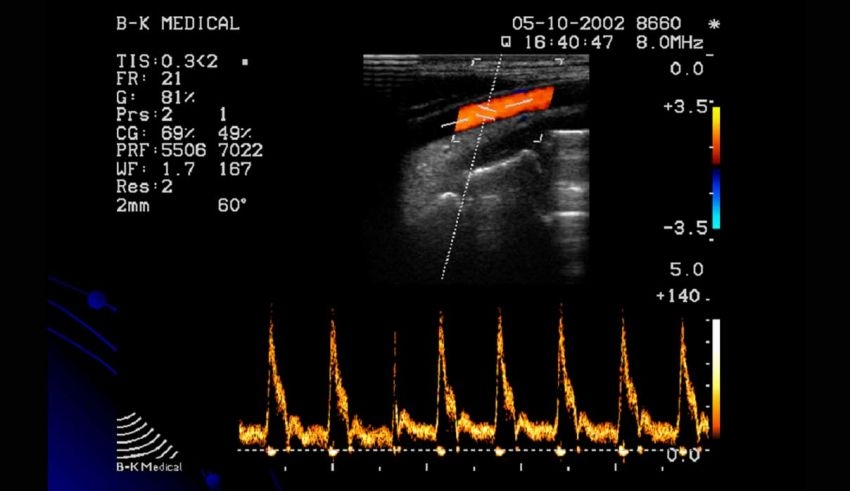

Doppler là tên của một dạng hiệu ứng dùng trong chẩn đoán hình ảnh y học. Kết quả thu được của hiệu ứng này là hình ảnh có sự chuyển động của các mô hoặc tế bào. Hiệu ứng doppler được dùng nhiều nhất đối với máu, chính xác hơn là kiểm tra tốc độ di chuyển của hồng cầu.

Hình ảnh của siêu âm doppler màu sẽ được thực hiện và thu về cùng với một dạng dữ liệu nữa là hình ảnh ở thang độ xám. Đây chính là hình ảnh siêu âm hai chiều phục vụ cho quá trình giải phẫu của bệnh nhân (nếu cần).